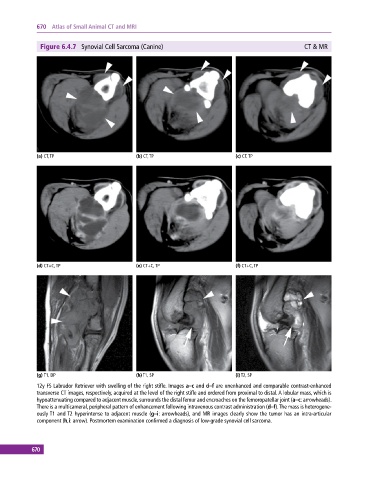

Figure 6.4.7 Synovial Cell Sarcoma (Canine) CT & MR

(a) CT, TP (b) CT, TP (c) CT, TP

(d) CT+C, TP (e) CT+C, TP (f) CT+C, TP

(g) T1, DP (h) T1, SP (i) T2, SP

12y FS Labrador Retriever with swelling of the right stifle. Images a–c and d–f are unenhanced and comparable contrast‐enhanced

transverse CT images, respectively, acquired at the level of the right stifle and ordered from proximal to distal. A lobular mass, which is

hypoattenuating compared to adjacent muscle, surrounds the distal femur and encroaches on the femoropatellar joint (a–c: arrowheads).

There is a multicameral, peripheral pattern of enhancement following intravenous contrast administration (d–f). The mass is heterogene-

ously T1 and T2 hyperintense to adjacent muscle (g–i: arrowheads), and MR images clearly show the tumor has an intra‐articular

component (h,i: arrow). Postmortem examination confirmed a diagnosis of low‐grade synovial cell sarcoma.